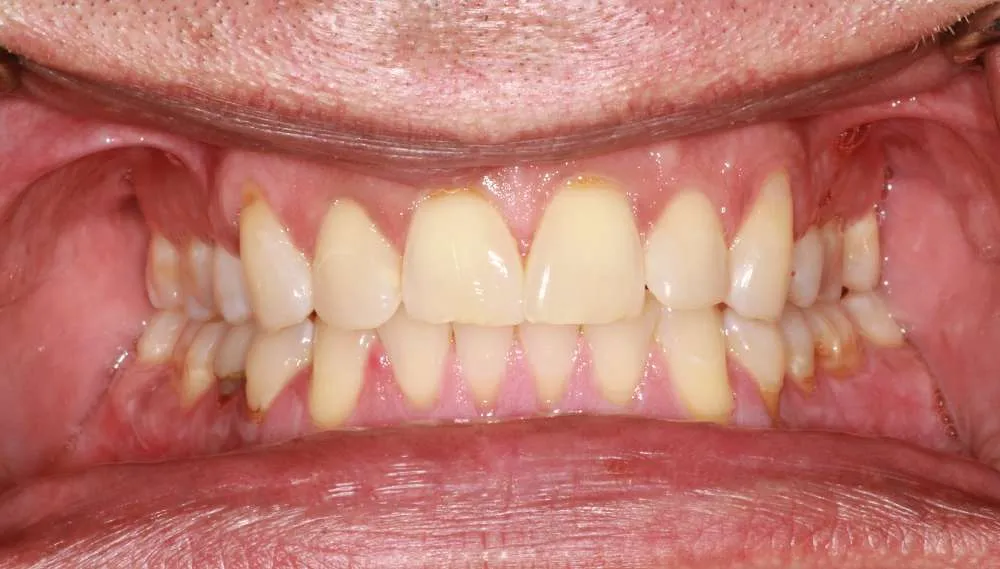

Real Stories, Real Results: Case Studies Showcasing How Our Personalized Approach Transforms Smiles and Lives

Complex Cases

Witness the Remarkable Changes We Can Achieve

While ultra-thin veneers are a fantastic option for many patients looking to enhance their smile, they may not be suitable for everyone. Ideal candidates are those with healthy teeth and gums who are looking to correct cosmetic issues like discoloration, misalignment/crooked or small gaps. During your consultation, Dr. O'Malley will assess your dental health and determine if ultra-thin veneers are the right choice for you.